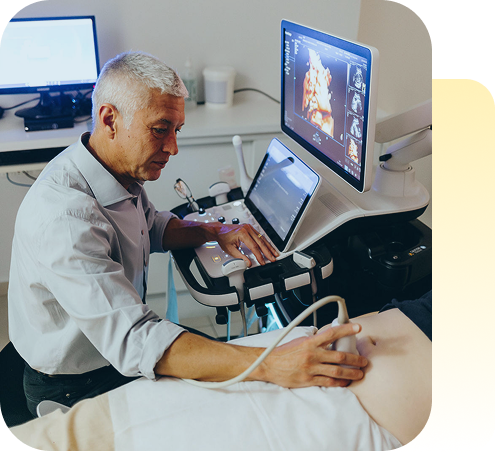

Quem é o

Dr. Fábio Peralta

Dr. Cleissom Fábio Andreoli Peralta, mais conhecido como Fábio Peralta, formou-se em Medicina pela Faculdade de Medicina de Ribeirão Preto (USP) em 1993 e concluiu sua Residência em Ginecologia e Obstetrícia entre 1995 e 1997 na mesma instituição. Com mestrado (2001) e doutorado (2003) em Obstetrícia e Ginecologia pela USP em São Paulo, realizou pós-doutorado em Medicina Fetal no King's College Hospital, em Londres, entre 2003 e 2004. É titular em Ginecologia e Obstetrícia, Ultrassonografia Geral e Medicina Fetal pelas principais sociedades brasileiras, além de possuir Diploma Internacional em Medicina Fetal pela Fetal Medicine Foundation.

Atualmente, dedica-se à formação de novos especialistas como responsável pelo curso de Pós-graduação em Medicina Fetal no CETRUS, lidera o Centro de Medicina e Cirurgia Fetal Gestar e coordena o serviço de Cirurgia Fetal no Hospital do Coração (HCor) em São Paulo.